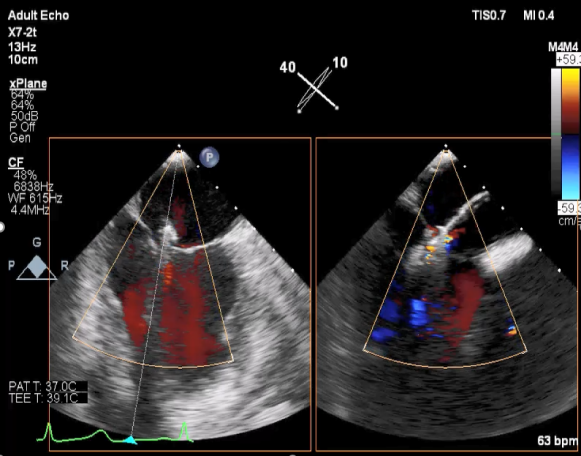

二尖瓣联合部切面引导第一枚XTR夹子转向病变区域并逐渐进入左室

第一枚XTR夹子到达病变区域捕获瓣叶并逐渐夹闭

XTR夹子释放,残余部分返流

三维超声心动图显示第一枚XTR夹子释放,残余返流主要位于外侧

引导第二枚XTR夹子转向外侧残余病变区域并逐渐进入左室

第二枚XTR夹子释放,返流明显减少

三维超声心动图显示第二枚XTR夹子释放